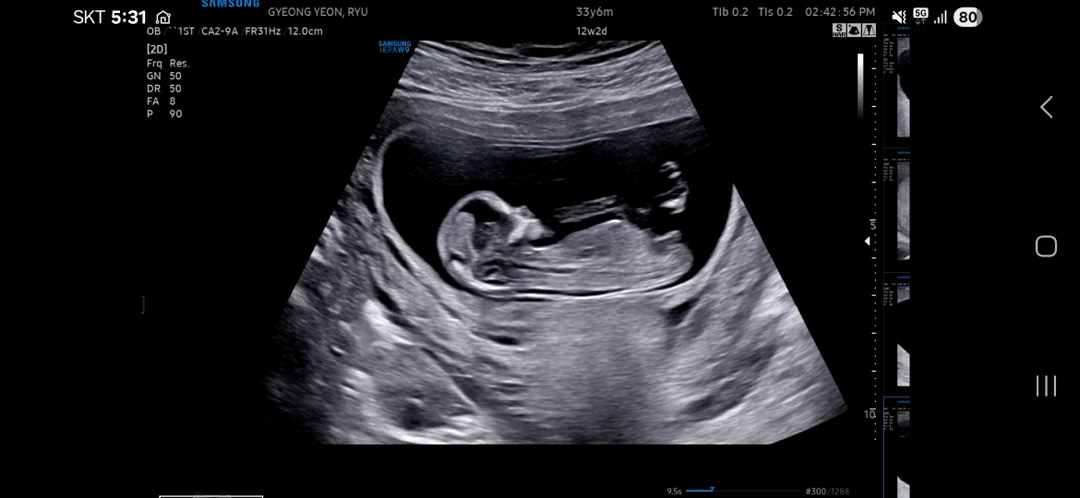

12주 각도법좀 봐주세요❤️

혹시 이사진으로 알수있을까요..?

아들같아요